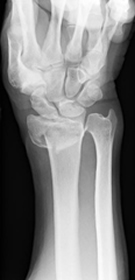

1. 橈骨遠位端骨折

粉砕の強い場合、関節内に骨折が及ぶ場合は手術を行います。プレートを用いた整復固定を行いますが、粉砕の強い場合は創外固定や人工骨充填を併用します。

また、当院では関節面に骨折線が及ぶ骨折に関しては、関節鏡を併用することによる、正確な関節面の整復を心がけています。術後の関節の変形による疼痛を予防します。